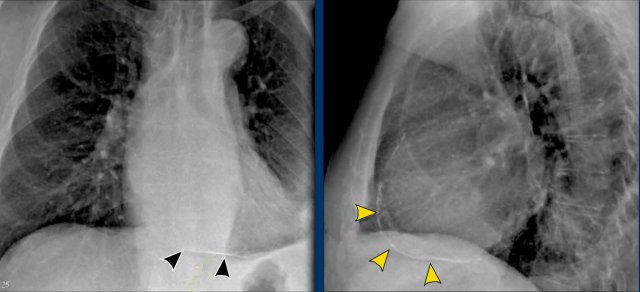

Displacement of the Azygoesophageal Line (1) – Hiatal hernia

A hiatal hernia (arrowheads) is the most common cause of displacement of the azygoesophageal line as seen on the PA-view.

Notice the air within the hernia on the lateral view (black arrow).